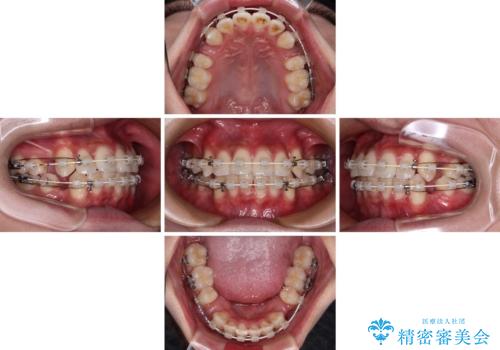

- 矯正装置

- 審美装置

- 2年2ヶ月

- 10-30回